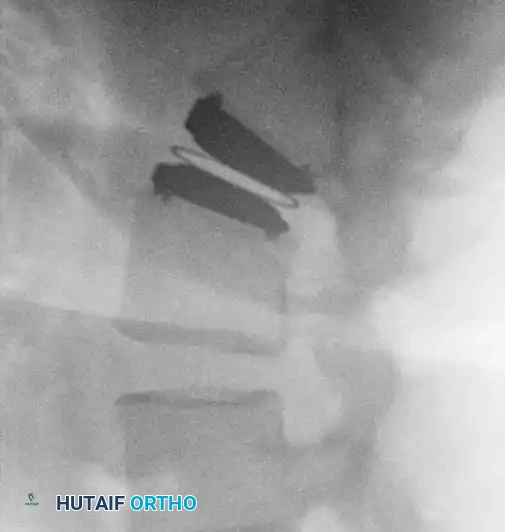

Fig. 39-47 A and B, Anteroposterior and lateral views of a patient with internal disc derangement treated with Charité total disc replacement.

The Charité Total Disc Replacement (TDR) represents a historical milestone in this biomechanical approach. It consists of two metallic endplates (typically cobalt-chromium-molybdenum) and a mobile ultra-high-molecular-weight polyethylene (UHMWPE) sliding core.